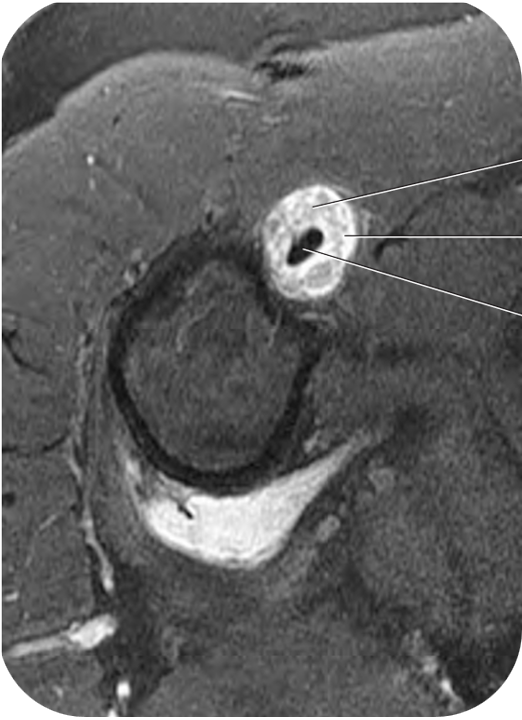

Q. En la siguiente imagen de resonancia magnética en corte axial, ¿Cuál es el hallazgo principal y a que patología corresponde?

A

Engrosamiento hiperintenso que rodea el tendón del bíceps en su porción vertical, en relación con Tenosinovitis